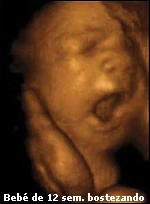

Un cosita: el feto de la ecografía en 4D de la foto no tiene 12 semanas, sino muchas más; tantas que, si saliese del útero de la mujer que lo gesta o gestaba (ignoro si ha nacido), podría sobrevivir perfectamente en una incubadora y, si mi apuras, casi sin ella. Ese feto es un señor feto que ha dejado muy atrás el primer trimestre de gestación. Hay que ceñirse a la realidad.

El ginecólogo que ha puesto estas fotos hechas en 2D-3D-4D solo de 12 semanas de gestación le he pasado tu comentario. Quizas el piense que tu haces ecografias tambien y tienes que renovarte la licencia.

El que ha hecho las ecografías lo sabe, el que ha incluido la información «feto de 12 semanas» al pie de la foto está al tanto y cualquier persona con un mínimo de conocimientos de biología sabe que ese feto no tiene cara ni aspecto de uno de tan sólo tres meses. Y por mí punto final a una discusión estéril y absurda.

Desde luego tu no estas licenciada en ciencias, ni medicina, ni Biología, ni Bioquímica. Esa foto corresponde a la 12 semana de gestación.